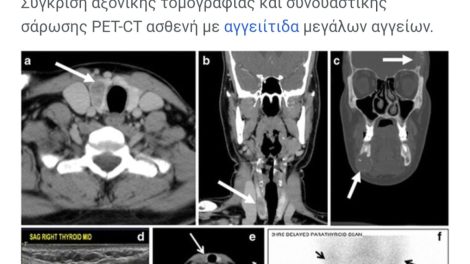

Aξονική τομογραφία (a, b, c), υπέρηχος (d), σάρωση SPECT-CT (e) και σπινθηρογράφημα (f) ασθενή με αδένωμα παραθυρεοειδούς (με άσπρα βέλη).[1] Οι...